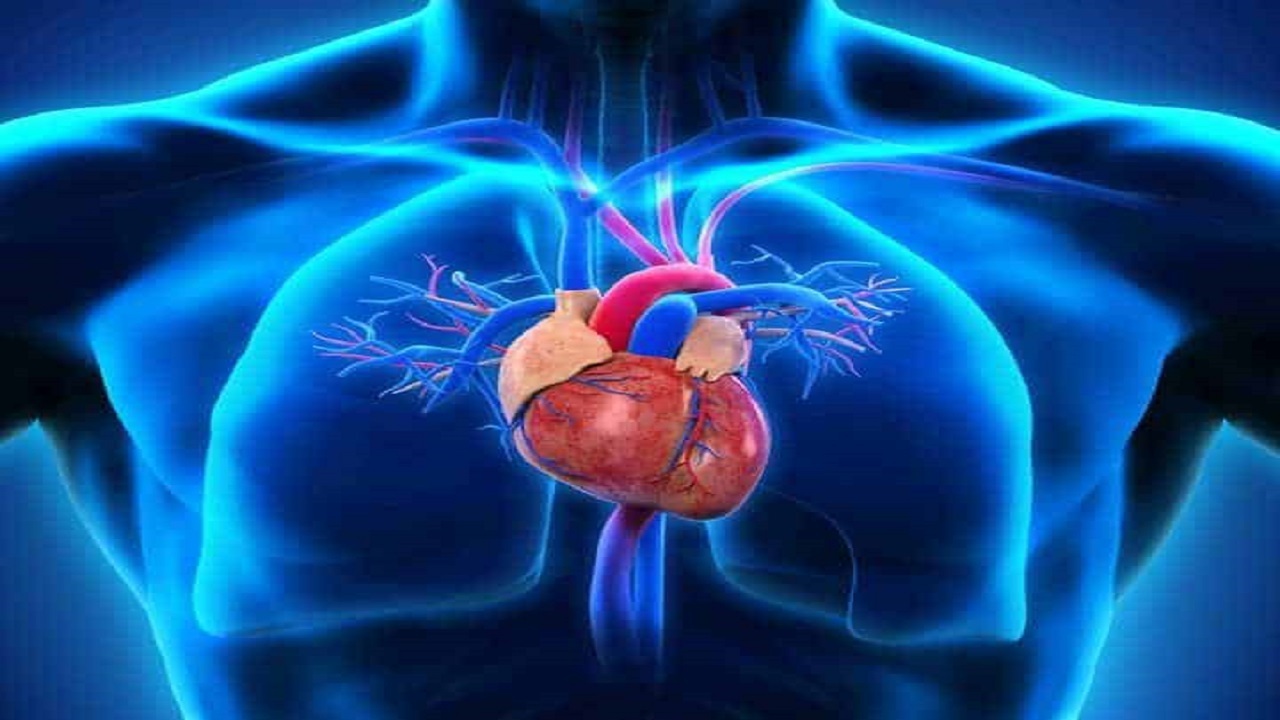

به گزارش خبرگزاری صدا و سیما، مرکز البرز؛ عضو هیات علمی دانشگاه علومپزشکی البرز همزمان با هفتم مهر روز جهانی قلب به علائم هشداردهنده بیماریهای